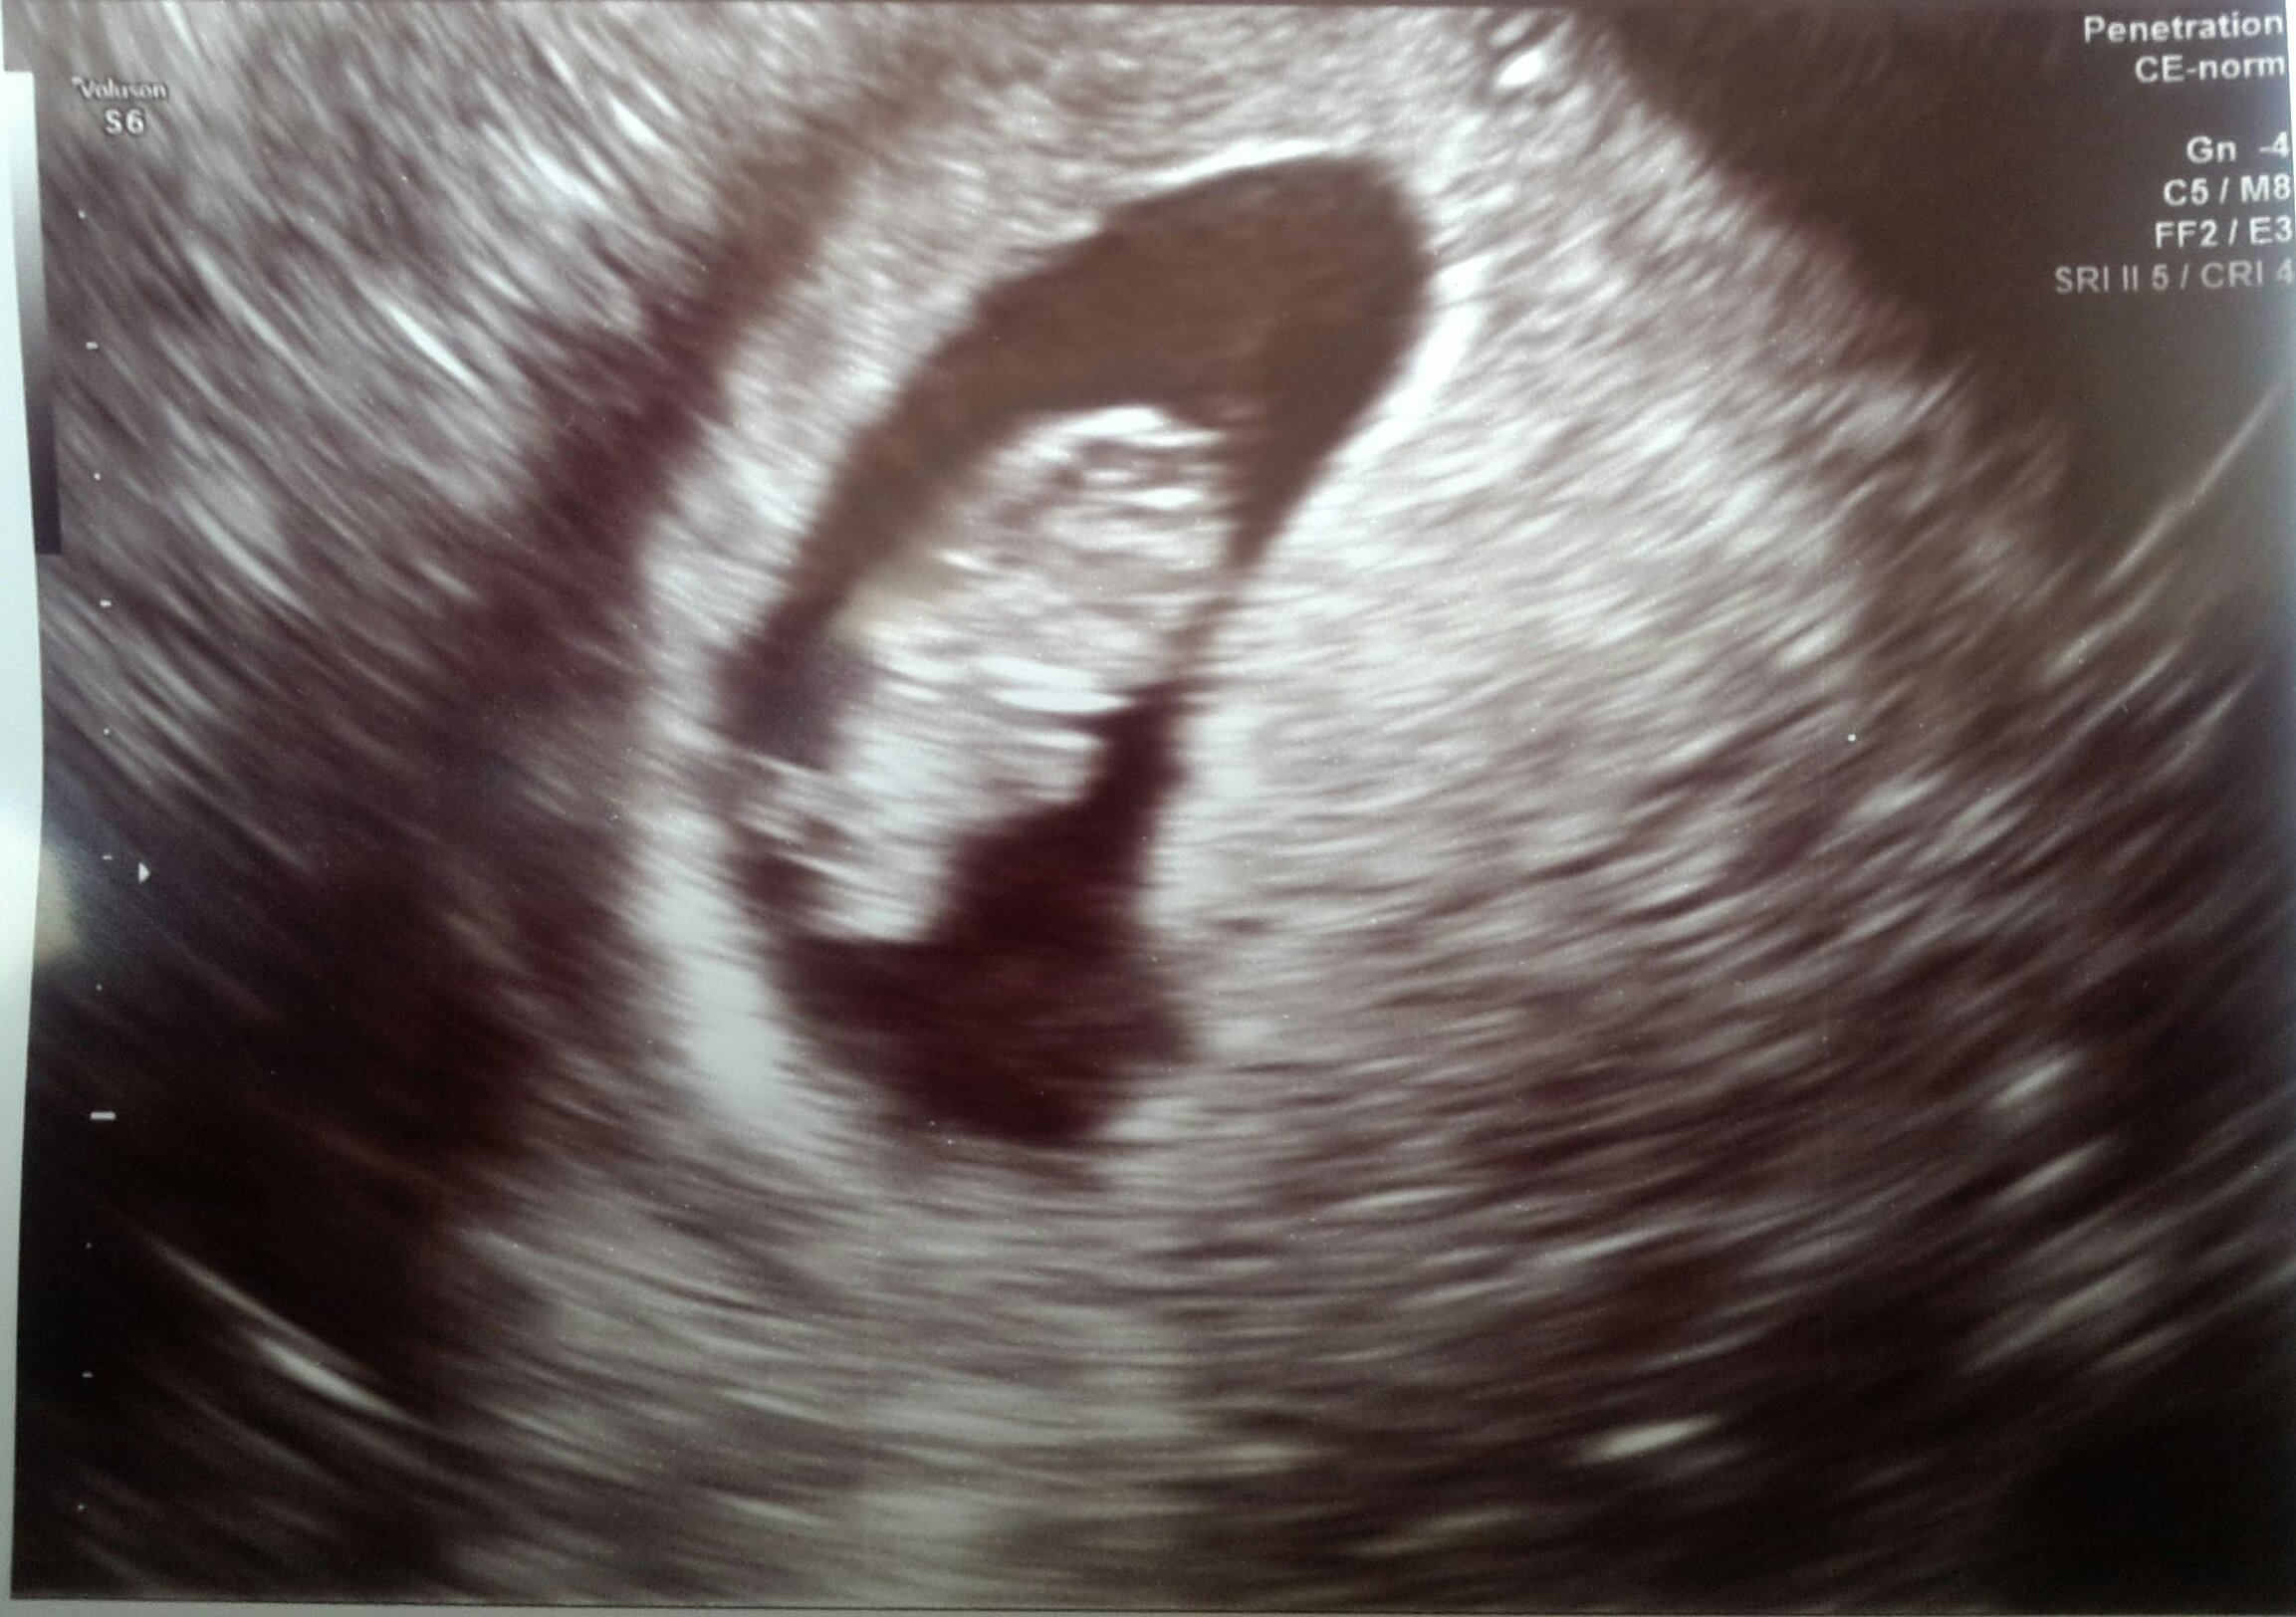

Had an unexpected US today due to some cramping. I was so expecting the worst... I am my own worst enemy but, baby has once again doubled in size from last Friday 8.21.15 to today 8.28.15!! Heartbeat today was up from 165 to 182!!!! We also got to see he/she wiggle which brought tears to my fiancées eyes... And in turn I cried. Tears of joy!! Keeping all of you in my thoughts! Positive vibes your way!